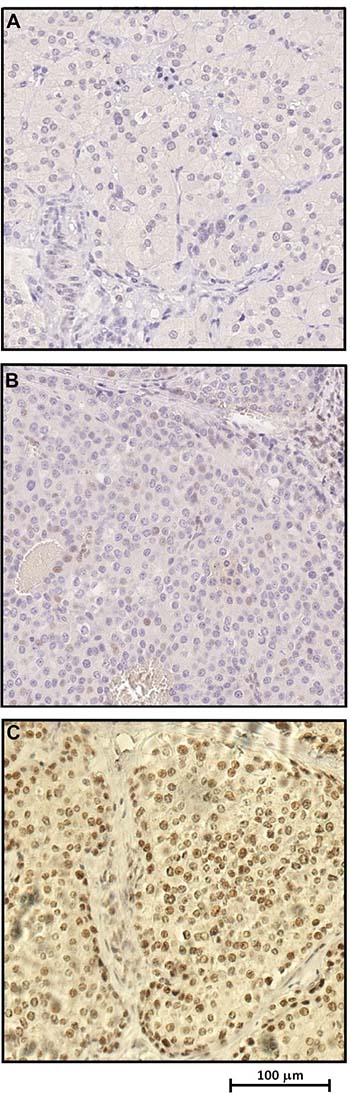

Immunoistochemical (IHC) analysis showed complete loss, or considerable reduction, respectively, of parafibromin nuclear expression on parathyroid tumour tissues belonging to two affected patients (II:3 and II:4) compared to the normal tissue (Figure 3A–3C, respectively).

Figure 3: Immunohistochemical analysis revealing loss or significant reduction of parafibromin nuclear expression respectively in parathyroid carcinoma tissue samples (A–B) compared to unaffected parathyroid tissue (C).